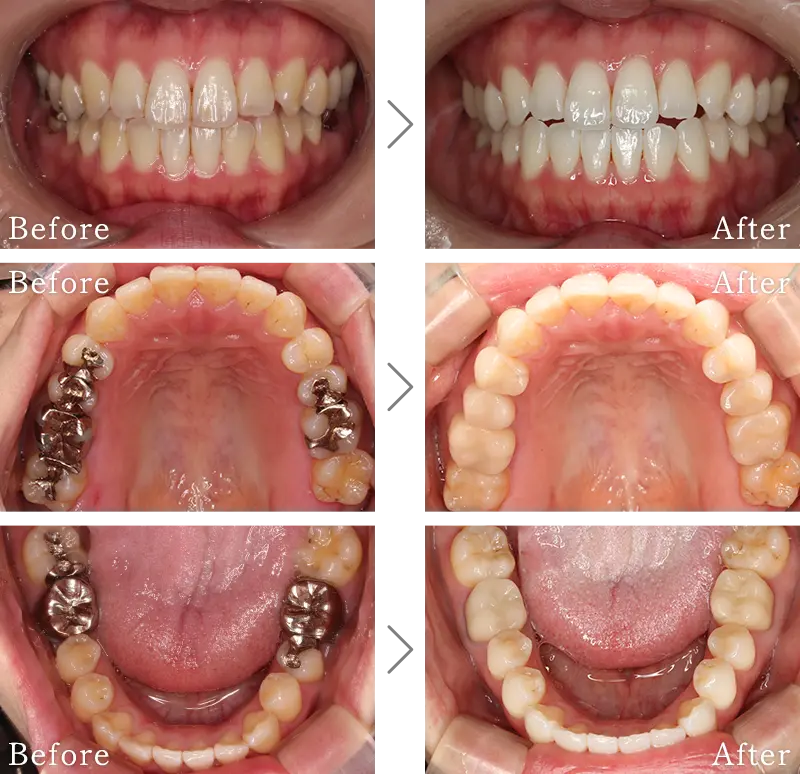

セラミックは、豊富な色調と特有の透明感があり天然歯と色調を合わせることができます。また、保険適応のプラスチック素材と違い、セラミックは物性が化学的に安定しているので、しっかりメインテナンスすれば長年使用していても変形や変色はほぼありません。

銀歯やプラスチックの詰め物・被せ物は、長年使用すると徐々に変形し、虫歯再発の大きな原因となります。しかし、セラミックは物性が化学的に安定しているので変形することがなく、虫歯の再発リスクを大きく減らします。また、セラミック特有の滑らかな表面が汚れが付きにくくし、歯周病の誘発を抑える特長もあります。

保険適用の銀歯に含まれているパラジウムや銀は金属アレルギーになりやすい物質の為、身体に良い素材と言えません。しかしメタルフリーであるセラミック治療では、非金属であるセラミックのみを使って治療を行いますので、金属アレルギーの方でも安心して治療をお受けいただけます。